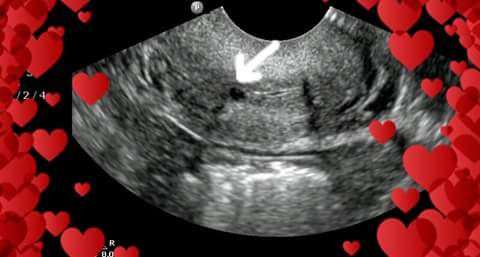

Lina в Зачатие 7 лет Снимок узи Как думаете , что это? Посмотрите еще 20 записей на эту тему Отменить Ответить Татьяна Да-да, плодное яйцо) поздравляю!) 17.08.2018 Ответить Lina Спасибо. 18.08.2018 Ответить Lina А оно в матке? 18.08.2018 Ответить Наташа Конечно в матке) 18.08.2018 Ответить Наташа Вы меня простите но у вас 3 детей неужели вы не разберётесь в этом? 18.08.2018 Ответить Lina У меня 1 ребенок. И я так не загонялась с ним. Я на 4 месяце только о беременности узнала :) 18.08.2018 Ответить Наташа Ого а почему на 4 только 18.08.2018 Ответить Lina Шли месики 18.08.2018 Ответить Lina Спасибо 18.08.2018 Ответить Наташа Вообще-то на плодное яйцо похоже) да мне тоде интересно вам что не сказали 17.08.2018 Ответить Lina Спасибо. Ниже ответила 17.08.2018 Ответить Bandy На УЗИ всегда заключение пишут. ☺️ 17.08.2018 Ответить Lina Не получила еще 17.08.2018 Ответить Кроха буду мамой Вам на узи не рассказали, что это? 17.08.2018 Ответить Lina Тут не говорят. Нужно ждать заключения от доктора 17.08.2018 Ответить Зимушка Похоже очень на плодное яйцо...но я не спец в узи 17.08.2018 Ответить Lina Спасибо 17.08.2018 Ответить Когда ты по жизни неудачник Молочница? Чаты Беременных Выберите чат: Январята-2026 Февралята-2026 Мартята-2026 Апрелята-2026 Майчата-2026 Июнята-2026 Июлята-2026 Августята-2026